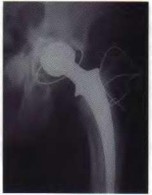

You are reviewing the wear characteristics of total hip arthroplasty (THA) bearing surfaces. The introduction of highly cross-linked polyethylene (HXLPE) has significantly reduced volumetric wear rates. Which of the following processing steps in HXLPE manufacturing is directly responsible for a decrease in the material's fracture toughness?

Highly cross-linked polyethylene requires irradiation to form cross-links (which improves wear resistance) but this process generates free radicals. To prevent oxidation, the material undergoes thermal processing. Post-irradiation remelting (heating above the melting point) effectively eliminates free radicals but significantly decreases the material's crystallinity, which compromises its ultimate tensile strength, fatigue strength, and fracture toughness. Annealing or utilizing Vitamin E are alternatives to preserve mechanical properties.